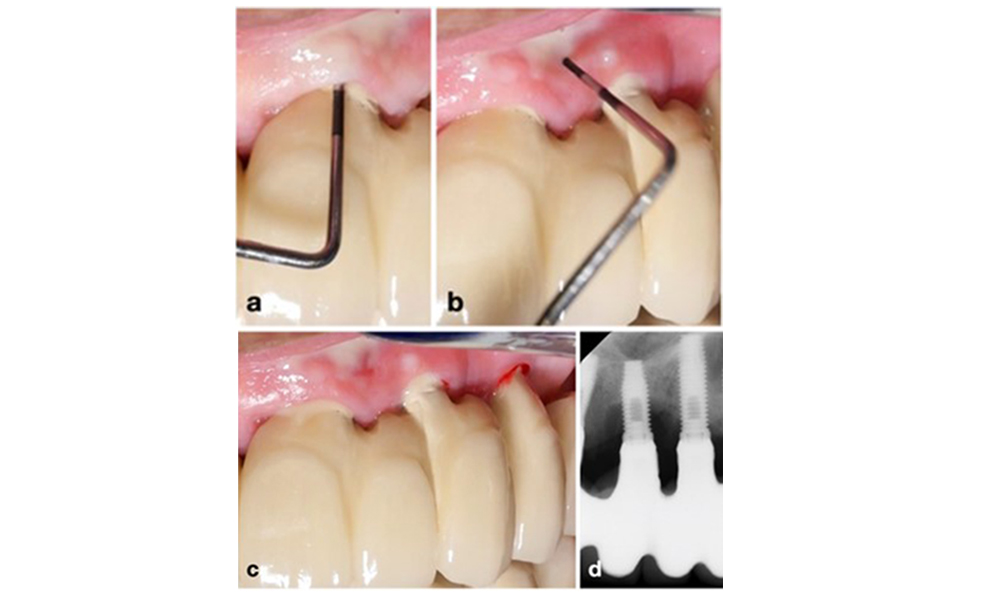

Management of peri-implantitis at implants judged as treatable consists of a non-surgical phase, which is often followed by surgical intervention. For the non-surgical approach, similar measures as those applied for the treatment of peri-implant mucositis are used; based on laboratory experiments air-polishing devices with a subgingival nozzle appear to provide certain advantages in terms of biofilm removal, compared to hand- or ultrasonic instruments (Herrera et al. 2023; Moharrami et al. 2019; Ronay et al. 2017) (figure 9).

Patient case with peri-implantitis. The non-surgical treatment is performed by using the supragingival (a-b) and subgingival handpiece of an air-polishing device (c-d). Removing the supra-construction provides better access to the implant surface (d).

Figure 9. Patient case with peri-implantitis. The non-surgical treatment is performed by using the supragingival (a-b) and subgingival handpiece of an air-polishing device (c-d). Removing the supra-construction provides better access to the implant surface (d).

Yet, the non-surgical approach often has limitations in accessing the implant surface, leading to insufficient decontamination. This is indeed reflected in the clinic, where disease resolution after non-surgical treatment of peri-implantitis is rather unpredictable and recurrence is observed for most cases, i.e., disease resolution was reported to occur only in less than every second case (Ramanauskaite et al. 2021). Therefore, the outcome of non-surgical treatment needs to be evaluated after about 6 weeks, and in cases of moderate or advanced peri-implantitis, surgery should be expected.